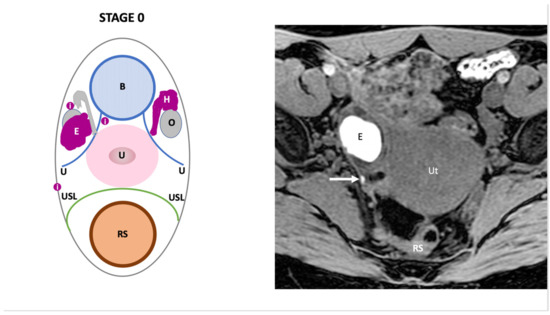

| Endo-Stage MRI 0 | Superficial endometriosis |

| Low |

| Endometriosis is strictly confined to the ovaries |

| ||